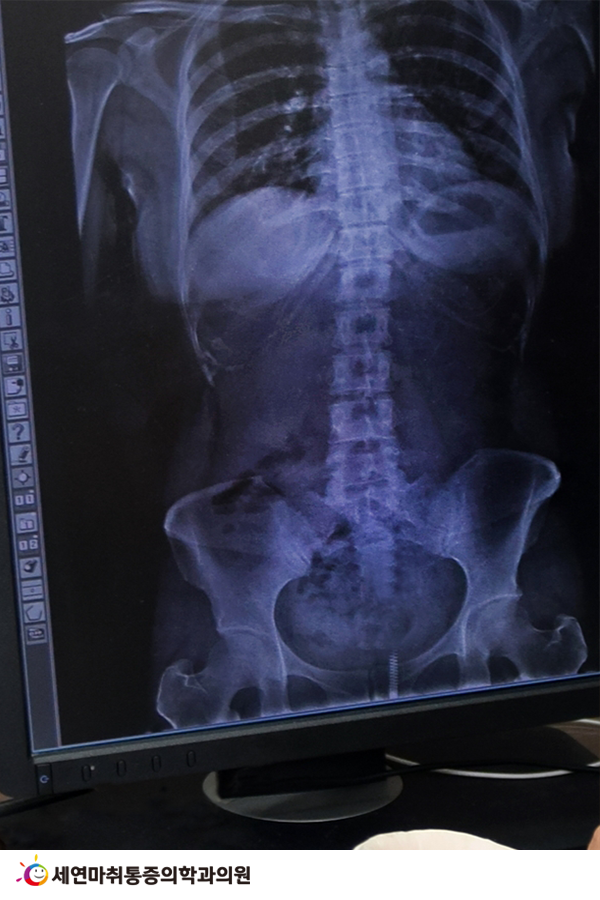

척추측만증은 주로 청소년기에 많이 나타나지만, 중년에 접어들었다면 퇴행성척추측만증 발생 위험도 커지므로 유의해야 합니다.

노화로 인한 척추질환은 여러 가지가 있지만, 그중 하나로 퇴행성척추측만증을 들 수 있습니다.

척추측만증을 척추옆굽음증이라고 하는데 말 그대로 척추가 옆으로 휘는 것을 말합니다. C자형, S자형으로 척추가 휘기도 하고 좌우로 몸이 기울거나 돌아가는 등 척추 변형이 생기는 질환입니다.

여기에 퇴행성이라는 단어가 붙으면 노화가 가장 직접적인 원인이 됩니다. 나이가 들면 뼈와 척추를 감싸고 받쳐주는 근육도 제 힘을 쓰지 못하면서 점점 척추에 변형이 생기는 것입니다.

주로 추간판(디스크)과 척추 후관절 부위에 퇴행성 변화가 일어나며, 척추 전체에 고르게 하중을 분산하지 못하고 비대칭적으로 하중을 전달하면서 퇴행성 척추측만증이 발생하는 것입니다.